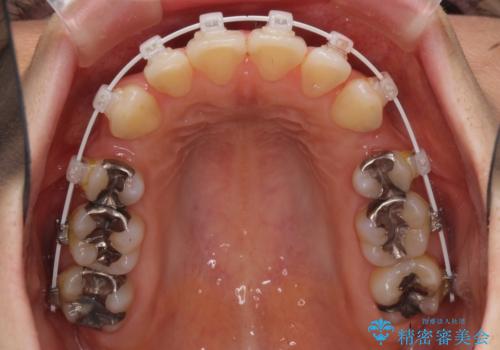

- 審美装置

- 上下の出っ歯を気にして来院された患者様です。

口元を積極的に引っ込めるために、上下左右の第一小臼歯を4本抜歯することとしました。

元々ディープバイトのため、スペースを閉じている期間に上下前歯が接触してしまい、治療期間が想定よりも伸びてしまいました。